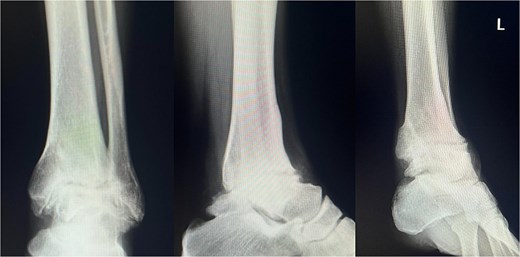

At 1.5 years, hardware removal was performed, with imaging confirming solid osseous union (Fig. 5). The Japanese Orthopaedic Association (JOA) score improved from 56.0 preoperatively to 81.4 at one year and 84.7 at the final 6.5-year follow-up. She resumed 60–70 matches per year without ankle pain, swelling, or motion-related discomfort. Her retirement after 6.5 years was unrelated to the ankle, resulting instead from cervical spine trauma and bilateral knee degeneration. Throughout follow-up, she remained free of ankle-related complications or functional restrictions.

Plain radiograph after hardware removal. At 1.5 years after surgery, the patient underwent hardware removal. Although the osteoarthritic changes in the subtalar joint have slightly progressed, radiographic evaluation confirmed solid osseous union at the tibiotalar joint.